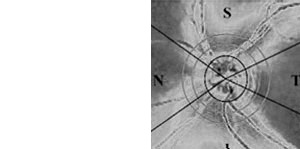

GDx Polarimetrie - Scanning-Laser-Polarimetrie

www.meditec.zeiss.com: GDx_Patient_Brochure_d.pdf